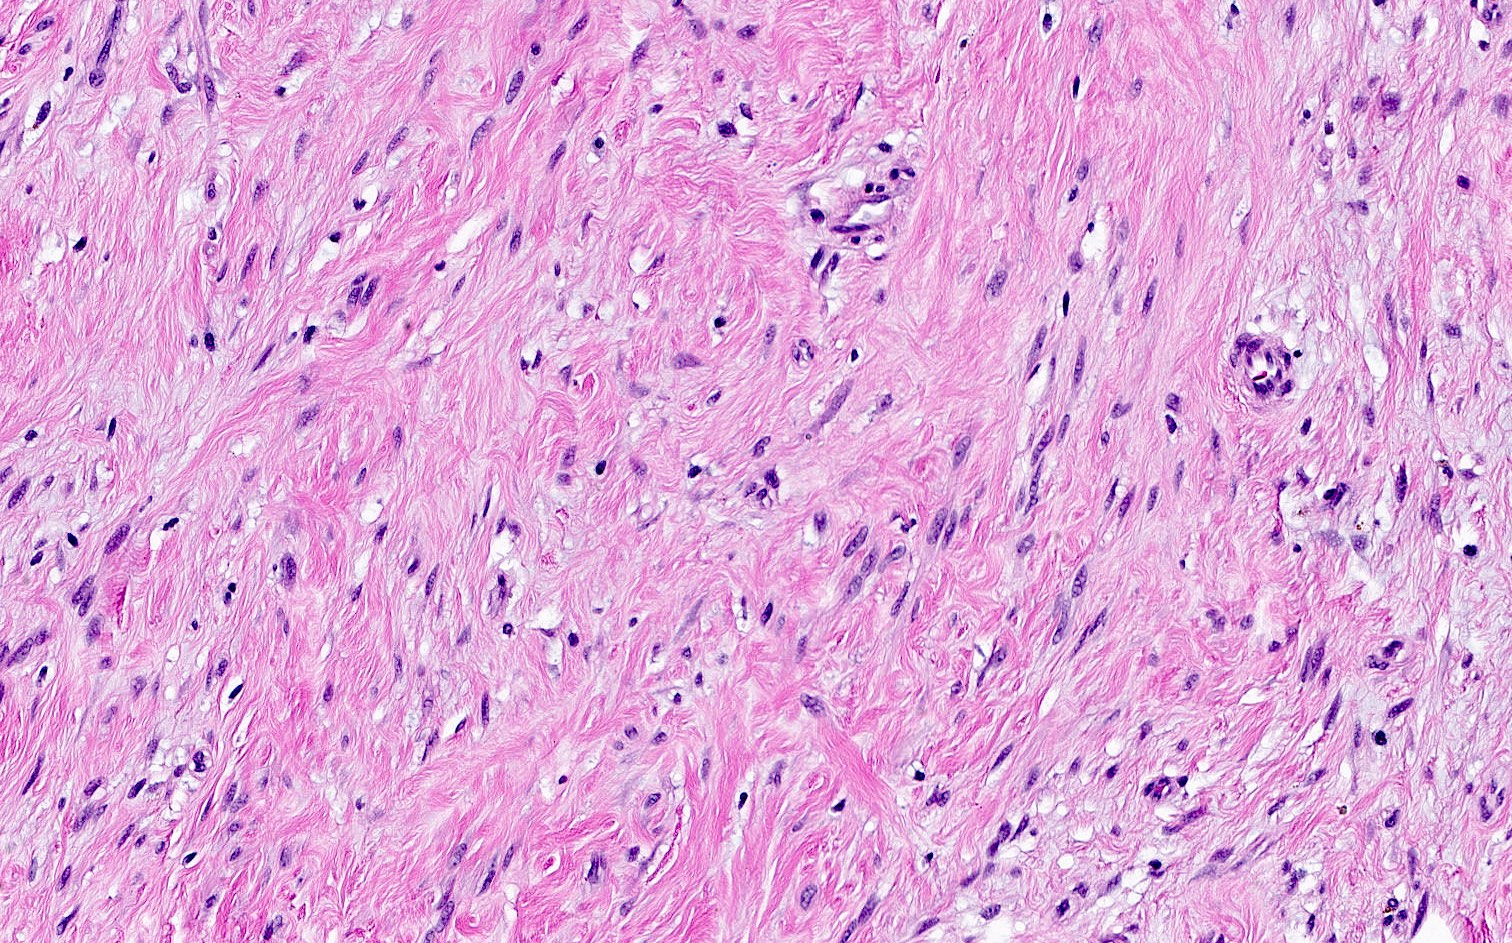

Microscopic (histologic) images

- Bland, uniform, short to elongated spindle cells arranged as short haphazard intersecting fascicles admixed with bands of hyalinized, brightly eosinophilic collagen and variable amounts of fat

- No more than mild nuclear atypia

- Mitoses usually absent, atypical mitoses and necrosis absent

- Focal myxoid stromal changes common

- Collagenized / fibrous: collagenous stroma predominates, may have hypocellular myofibroblastic spindle cell component